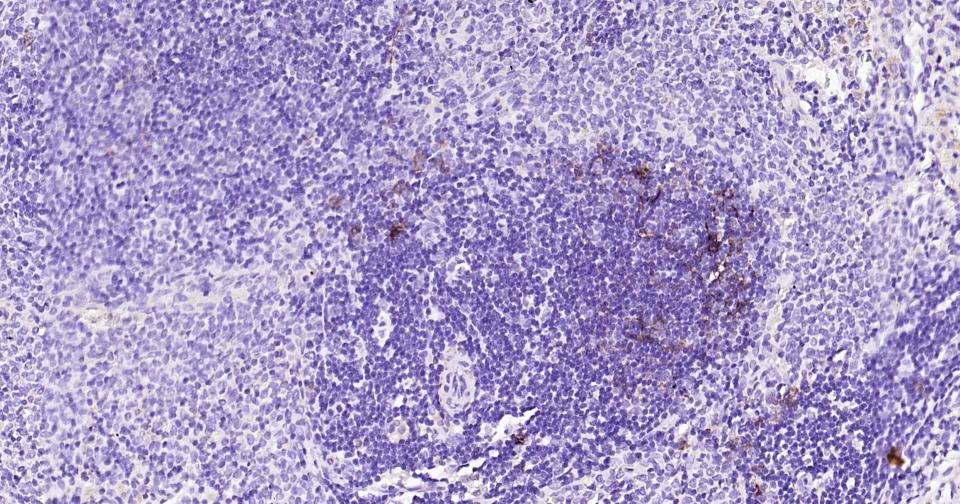

Paraformaldehyde-fixed, paraffin embedded Mouse Spleen; Antigen retrieval by boiling in sodium citrate buffer (pH6.0) for 15 min; Antibody incubation with NGFR/p75NTR Monoclonal Antibody, Unconjugated(bsm-52253R) at 1:200 overnight at 4°C, followed by conjugation to the bs-0295G-HRP and DAB (C-0010) staining.